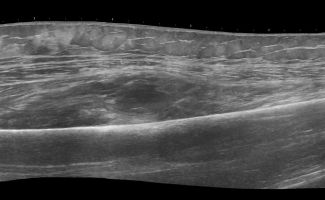

- Διάγνωση Μυϊκών Βλαβών: Το Υπερηχογράφημα Μυών επιτρέπει την αναγνώριση μυϊκών παθήσεων όπως τα αιματώματα, τα λιπώματα, τα νεοπλάσματα και η σημειολογία ασβεστοποιού μυοσίτιδας.

- Παρακολούθηση Ανάρρωσης: Η εξέταση μέσω Υπερηχογραφήματος επιτρέπει την παρακολούθηση της εξέλιξης της ανάρρωσης μετά από τραυματισμό ή πάθηση, προσφέροντας σημαντικές πληροφορίες σχετικά με το χρόνο επιστροφής στις κανονικές δραστηριότητες.